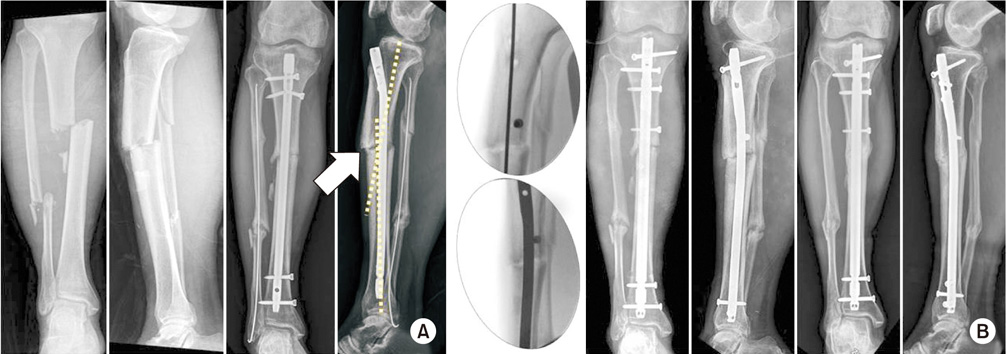

(A) A 23-year-old man presented varus deformity after conservative treatment from a left femoral fracture at childhood. Mechanical axis was slightly shifted to the medial side compared with the right side. (B) Physical examination showed that the position of the left foot was rotated inward, and a computed tomography scan confirmed an increased femoral internal rotation. (C) The metal pin was inserted parallel to the anterior femur and then percutaneously osteotomized. After that, the pins fixed in parallel were rotated to correct the desired degree of rotational alignment, and intramedullary nail was inserted. (D) After the correction, the mechanical axis was passed to the center of the knee and the operation was completed. The position of the foot was similar on both sides. (E) On postoperative radiographs, it was confirmed that varus deformity was corrected, and the osteotomy site showed minimal incision. (F) One year later, osteotomy was well united, angulation and rotational deformity were corrected, and the mechanical axis was restored.

Fig. 7 (A) A 23-year-old man presented varus deformity after conservative treatment from a left femoral fracture at childhood. Mechanical axis was slightly shifted to the medial side compared with the right side. (B) Physical examination showed that the position of the left foot was rotated inward, and a computed tomography scan confirmed an increased femoral internal rotation. (C) The metal pin was inserted parallel to the anterior femur and then percutaneously osteotomized. After that, the pins fixed in parallel were rotated to correct the desired degree of rotational alignment, and intramedullary nail was inserted. (D) After the correction, the mechanical axis was passed to the center of the knee and the operation was completed. The position of the foot was similar on both sides. (E) On postoperative radiographs, it was confirmed that varus deformity was corrected, and the osteotomy site showed minimal incision. (F) One year later, osteotomy was well united, angulation and rotational deformity were corrected, and the mechanical axis was restored.